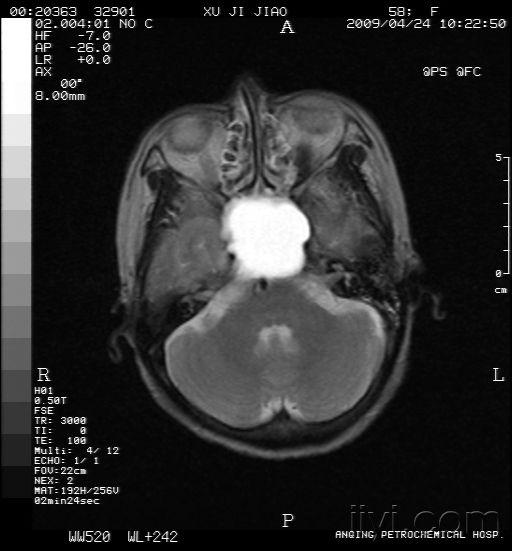

mri实图:蝶窦囊肿?请各位老师进来见图片

图片尺寸675x688